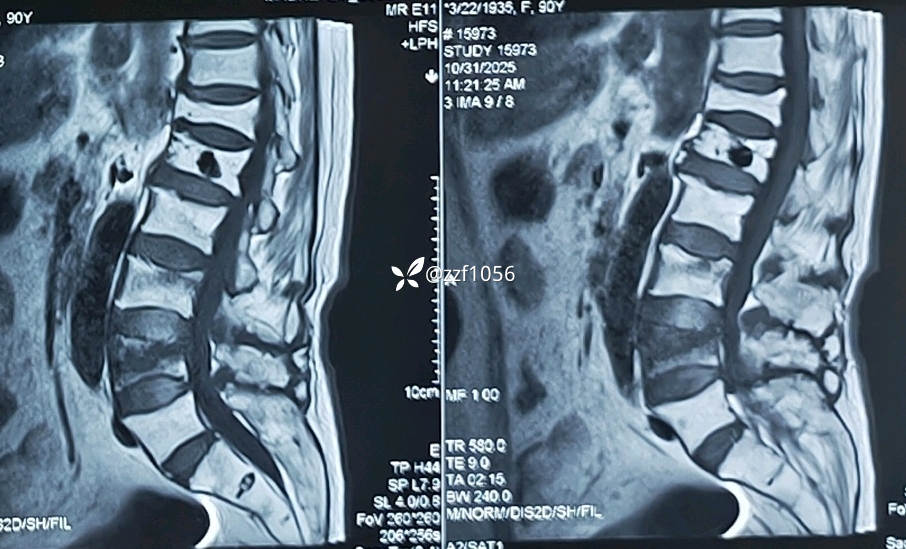

腰3腰4椎体压缩性骨折明确

收住院进一步ct检查

果不其然,骨水泥渗漏入椎管内,非常能感受到当时主刀惊出一身汗😓,万幸的是患者并没有神经症状。

给家属谈话沟通,现腰3腰4椎体压缩性骨折需要再次行椎体成形术,沟通过程中谈到了椎管渗漏风险,但未明确提示家属既往骨水泥漏入椎管情况。

患者90岁了,单侧穿刺,见好就收,快速收工

患者术后疼痛明显缓解,双下肢无神经症状